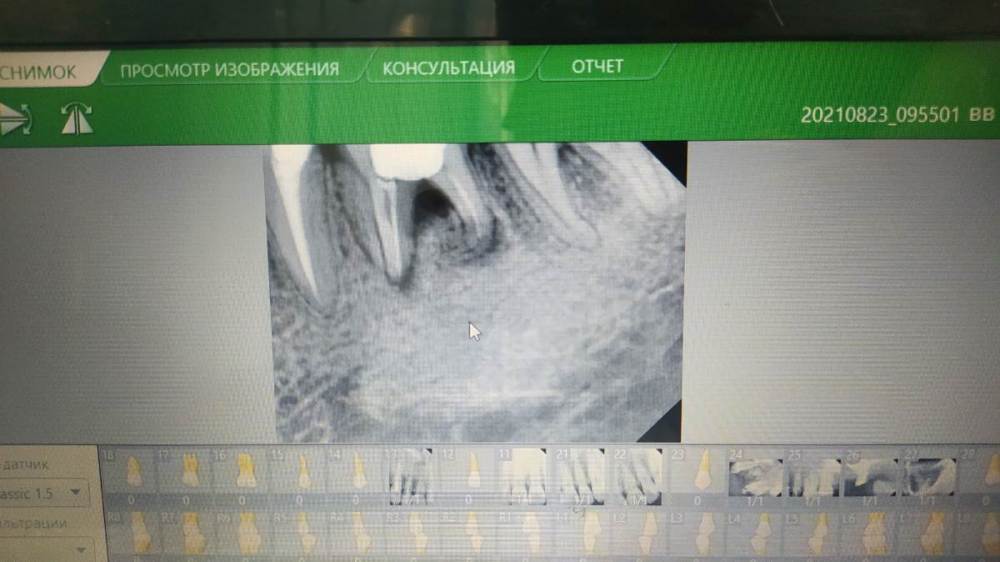

Mellonka Опубликовано 15 августа, 2022 Поделиться Опубликовано 15 августа, 2022 Что можно сделать с зубом? Стоматолог говорит, что только удалять, но возможно есть способ обойтись без этого. Ссылка на комментарий

Fin Опубликовано 15 августа, 2022 Поделиться Опубликовано 15 августа, 2022 (изменено) 2 часа назад, Mellonka сказал: Что можно сделать с зубом? Стоматолог говорит, что только удалять, но возможно есть способ обойтись без этого. К сожалению нет смысла пытаться спасти этот зуб, показания только к удалению. Изменено 15 августа, 2022 пользователем Fin 3 Ссылка на комментарий

wladdX Опубликовано 15 августа, 2022 Поделиться Опубликовано 15 августа, 2022 Удаляйте Ссылка на комментарий